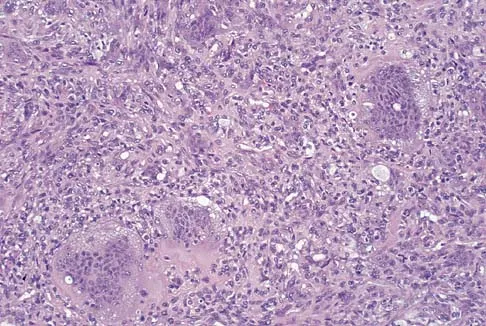

Question 24

Figures 27a through 27c show the AP radiograph, MRI scan, and biopsy specimen of an otherwise healthy man who has a painful wrist. Serum chemistry studies are normal. What is the most likely diagnosis?

Explanation